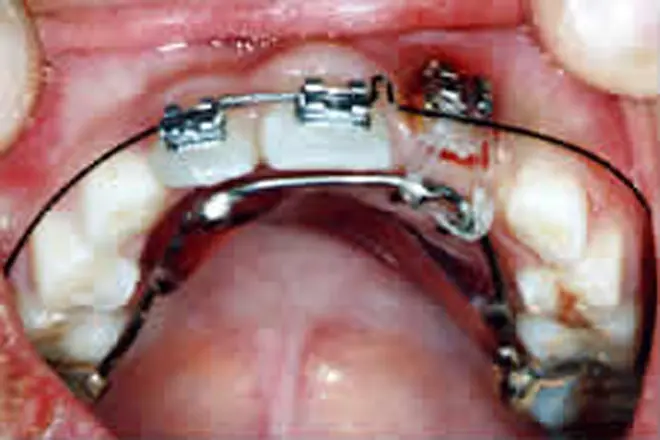

子どもの矯正 治療例2

まだ乳歯が多く残っていて、全体的な矯正治療はできません。そこで裏側に舌突出防止装置を付け、舌癖を改善して開咬を治療しました。

開咬が解消され、口をあけたときに前歯の隙間が出なくなりました。

| 患者さまの年齢・性別 | 9歳・女性 |

|---|---|

| 治療期間 | 1年 |

| 治療費(税込) | 165,000円 |

| 主訴 | 前歯で噛めない |

| 診断名・主な症状 | 開咬 |

| 治療に用いた主な装置 | 舌突出防止装置 |

| 治療内容 | 舌側に舌突出防止装置を付けることで、舌が前歯を押すのを防ぎます。 |

| 抜歯部位 | 非抜歯 |